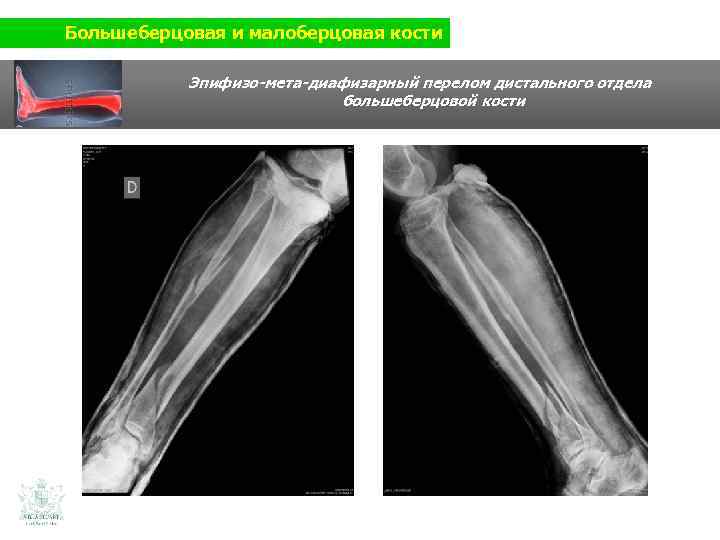

Большеберцовая и малоберцовая кости Клинический случай (большеберцовая и малоберцовая кости) Мужчина 60 ти лет Травма нижней конечности (авария на мотоцикле)

Большеберцовая и малоберцовая кости Эпифизо-мета-диафизарный перелом дистального отдела большеберцовой кости

Большеберцовая и малоберцовая кости Эпифизо-мета-диафизарный перелом дистального отдела большеберцовой кости Мини-инфазивный остеосинтез (пластины и винты)